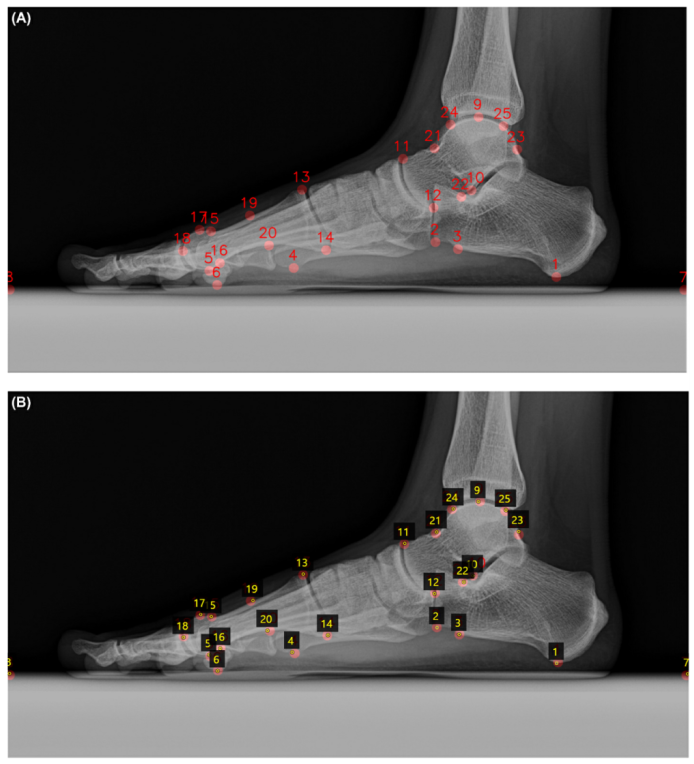

1*WUrGtAB8SKI5Z1QuCsK_Xg.png Figure 5. (A) 자동 식별된 예측 랜드마크. 이 예측 랜드마크는 가이드로 사용됨. (B) 자동 식별 가이드 하에 관찰자가 식별한 랜드마크 예시.